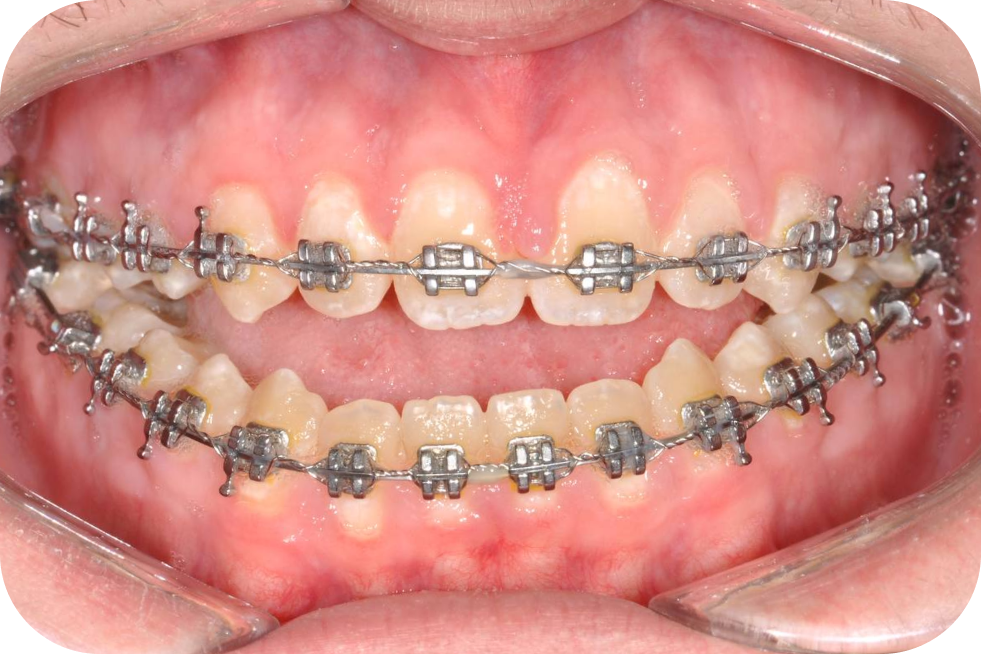

Положение зубов до начала лечения скомпенсировалось в соответствии с аномалией прикуса.

При подготовке будет происходить декомпенсация — зубные ряды выставляются в соответствии с правильным прикусом после операции.

Эстетически положение зубов до лечения может выглядеть лучше, чем во время подготовки. Например, если у вас дистальный прикус, то верхняя челюсть будет смотреться более громоздкой. Если мезиальный, то нижняя. К этому нужно быть готовым.